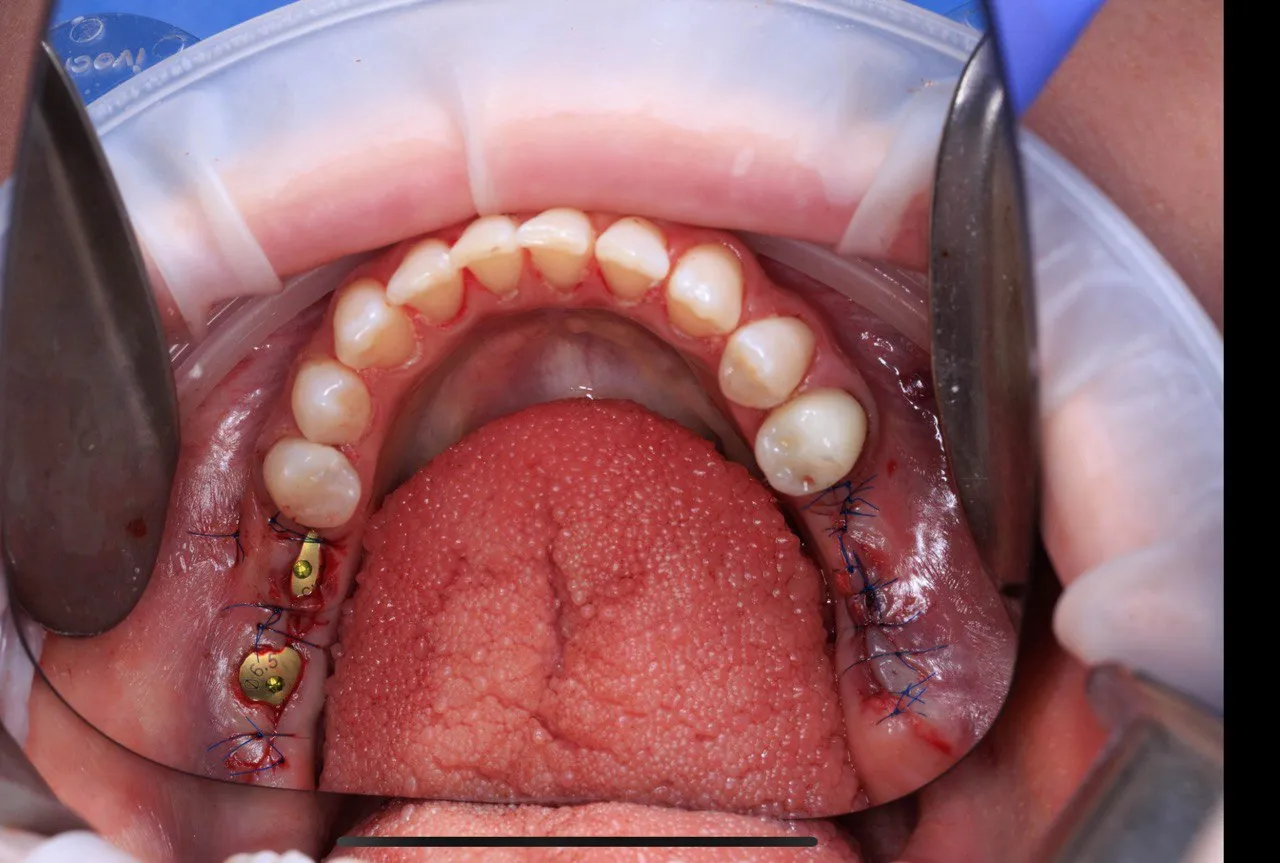

Dual Arch Rehabilitation — All-on-4 & All-on-6

Complete upper and lower jaw rehabilitation. All-on-4 concept for maxilla and All-on-6 for mandible with custom surgical guides.